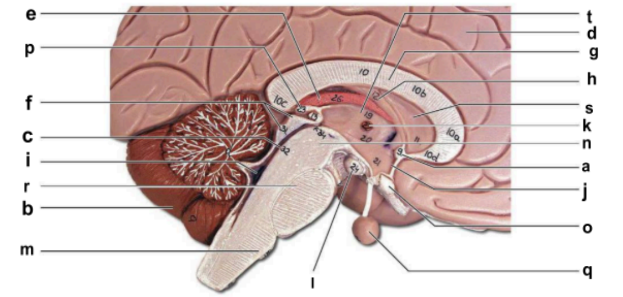

Identify the structure labeled “a” in the image.

anterior commissure

Identify the structure labeled “b” in the image.

cerebellum

Identify the structure labeled “c” in the image.

cerebral aqueduct

Identify the structure labeled “d” in the image.

cerebral hemisphere

Identify the structure labeled “e” in the image.

choroid plexus

Identify the structure labeled “f” in the image.

corpora quadrigemina

Identify the structure labeled “g” in the image.

corpos callosum

Identify the structure labeled “h” in the image.

fornix

Identify the structure labeled “i” in the image.

fourth ventricle

Identify the structure labeled “j” in the image.

hypothalamus

Identify the structure labeled “k” in the image.

interthalamic adhesion

Identify the structure labeled “l” in the image.

mammilary body

Identify the structure labeled “m” in the image.

medulla oblongata

Identify the structure labeled “n” in the image.

midbrain

Identify the structure labeled “o” in the image.

optic chiasma

Identify the structure labeled “p” in the image.

pineal gland

Identify the structure labeled “q” in the image.

pituitary gland

Identify the structure labeled “r” in the image.

pons

Identify the structure labeled “s” in the image.

septum pellucidum

Identify the structure labeled “t” in the image.

thalamus